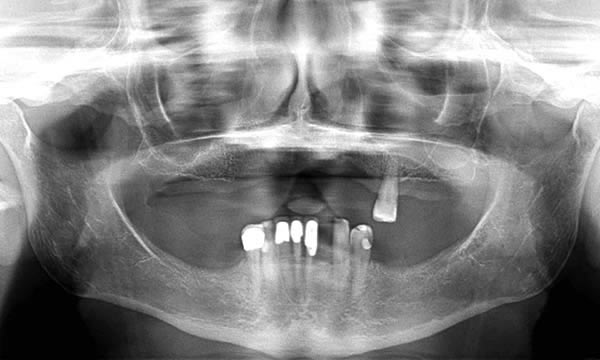

After many years of wearing a denture, this patient wanted a change to a fixed and conservative appliance. Two Astra EV implants were placed to support a four unit bridge.